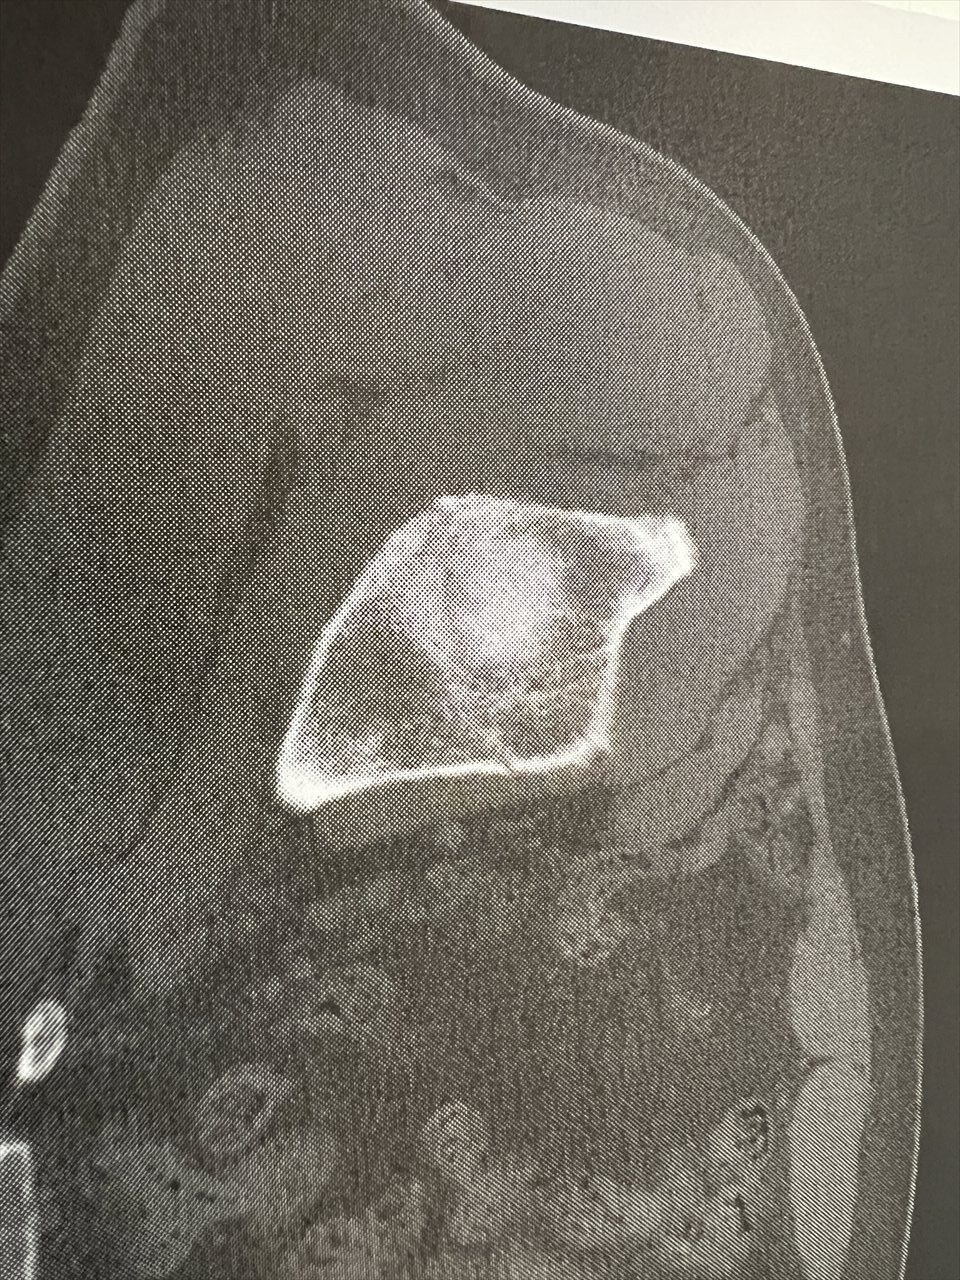

2ヶ月の長きに亘る入院生活も終わりを告げます。骨盤の骨折部分も概ね修復されました。CT写真のとおりです。

最初は、くっきりとスジが見えましたが、だんだんとぼけていき、最終的には、スジが見えなくなってきましたね。

8月9日は、はっきりとエッジのある亀裂が認められるが、10月9日は、完全にぼやけていて、亀裂が不明瞭。すなわち、亀裂がふさがったということですね。